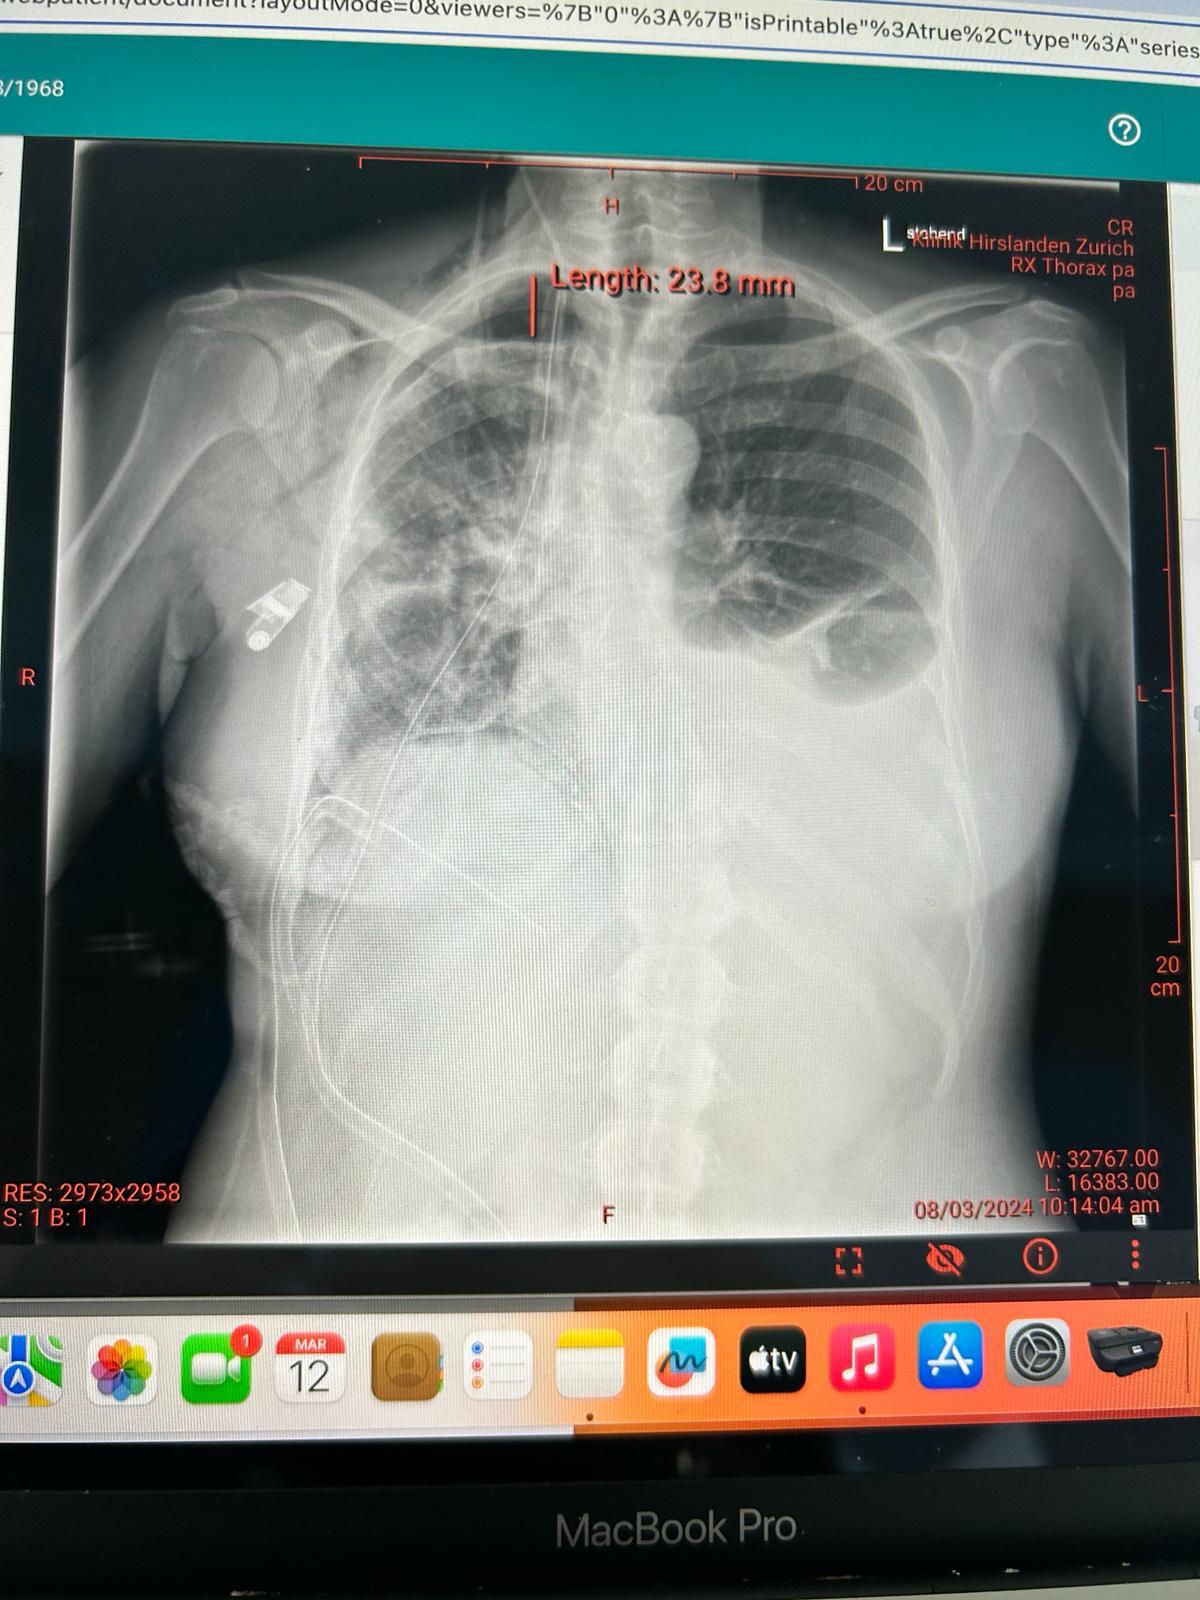

3. How is lung cancer diagnosed?

Doctors use imaging tests like X-rays or CT scans. If needed, a biopsy is performed to confirm the diagnosis.